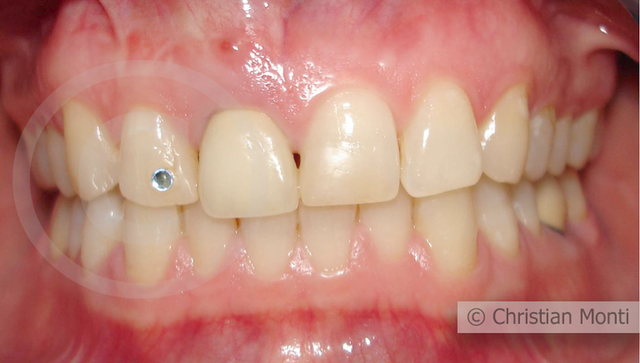

EDENTULIA SINGOLA

Impianto in sostituzione di un incisivo superiore